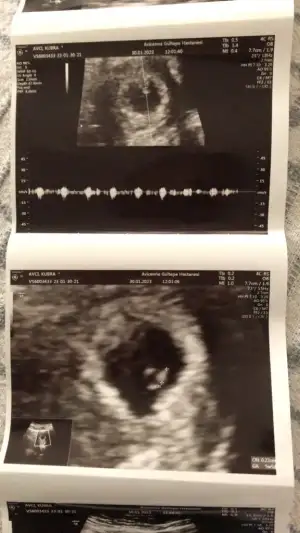

• IMG-20230130-WA0000.webp

IMG-20230130-WA0000.webp

33,4 KB · Görüntüleme: 97

• IMG-20230130-WA0001.webp

IMG-20230130-WA0001.webp

37,1 KB · Görüntüleme: 95

• IMG-20230130-WA0002.webp

IMG-20230130-WA0002.webp

32,2 KB · Görüntüleme: 91